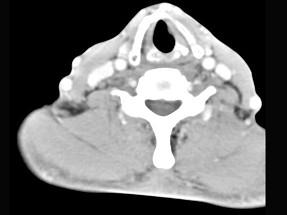

问题 男性,50岁,自觉咽喉部不适1个多月,间或刺激性咳嗽,CT扫描如图所示,请选择正确的描述和答案 ( )

选项 A、考虑为左侧声带乳头状瘤 B、考虑为喉癌 C、增强扫描结节强化不明显,密度均匀,周围结构未见受侵 D、考虑为左侧声带息肉 E、左侧声带内侧壁见结节状影向腔内突出,以宽基底与声带相连

答案 ACE